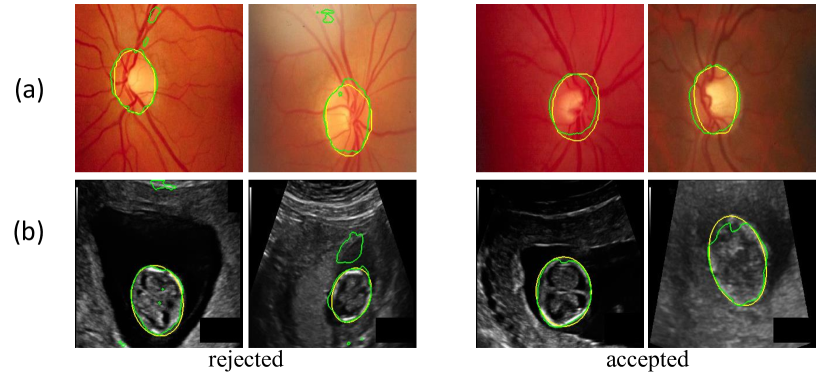

To validate our noise-robust iterative method to learn from noisy pseudo labels obtained by , we compared the following variants: 1) U-Net (baseline) that learns from the pseudo labels using a standard Dice loss without considering the existence of noise; 2) U-Net (MAE) that uses MAE loss [38] for training; 3) U-Net () that uses generalized cross entropy loss [40] for training; 4) U-Net trained with Dice loss from samples selected by our LQSS, which is referred to as U-Net (LQSS). These four methods only train the model once without iterative training, and were further compared with: 5) U-Net (LQSS + IT) that refers to U-Net (LQSS) followed by iterative training with Dice loss; and 6) U-Net (LQSS + IT + wDice) that refers to U-Net (LQSS) followed by iterative training with our noise-weighted Dice loss. For the last two variants, the round number determined by the validation set was 3 and 4 for optic disc segmentation and fetal head segmentation, respectively. The quantitative evaluation results are shown in Table 4, which shows that LQSS obtained better performance than the baseline, and using iterative training and noise-weighted Dice loss further improves the segmentation accuracy. Fig. 8 shows that our LQSS is able to reject low-quality pseudo labels with some noise, e.g., over segmentation with false positives. Note that in Fig. 8(a), the second rejected case of has a higher contrast than the first accepted case, which shows our LQSS does not tend to only select easy samples. Fig. 6 demonstrates the refinement of pseudo labels at different rounds of training stage. Fig. 9 shows the performance at different rounds of our iterative method to learn from noisy pseudo labels obtained by . It shows that the performance increased at the beginning and reached a plateau after two rounds for optic disc and three rounds for fetal head, and that noise-weighted Dice loss is better than Dice loss during the iterative training. We compared our ellipse-based shape prior with circle-based shape prior to obtain the pseudo labels, and they are denoted as U-Net (baseline) and U-Net (baseline)∘, respectively. Results in Table 4 show that modeling optic disc and fetal head as ellipses largely outperform modeling as circles.